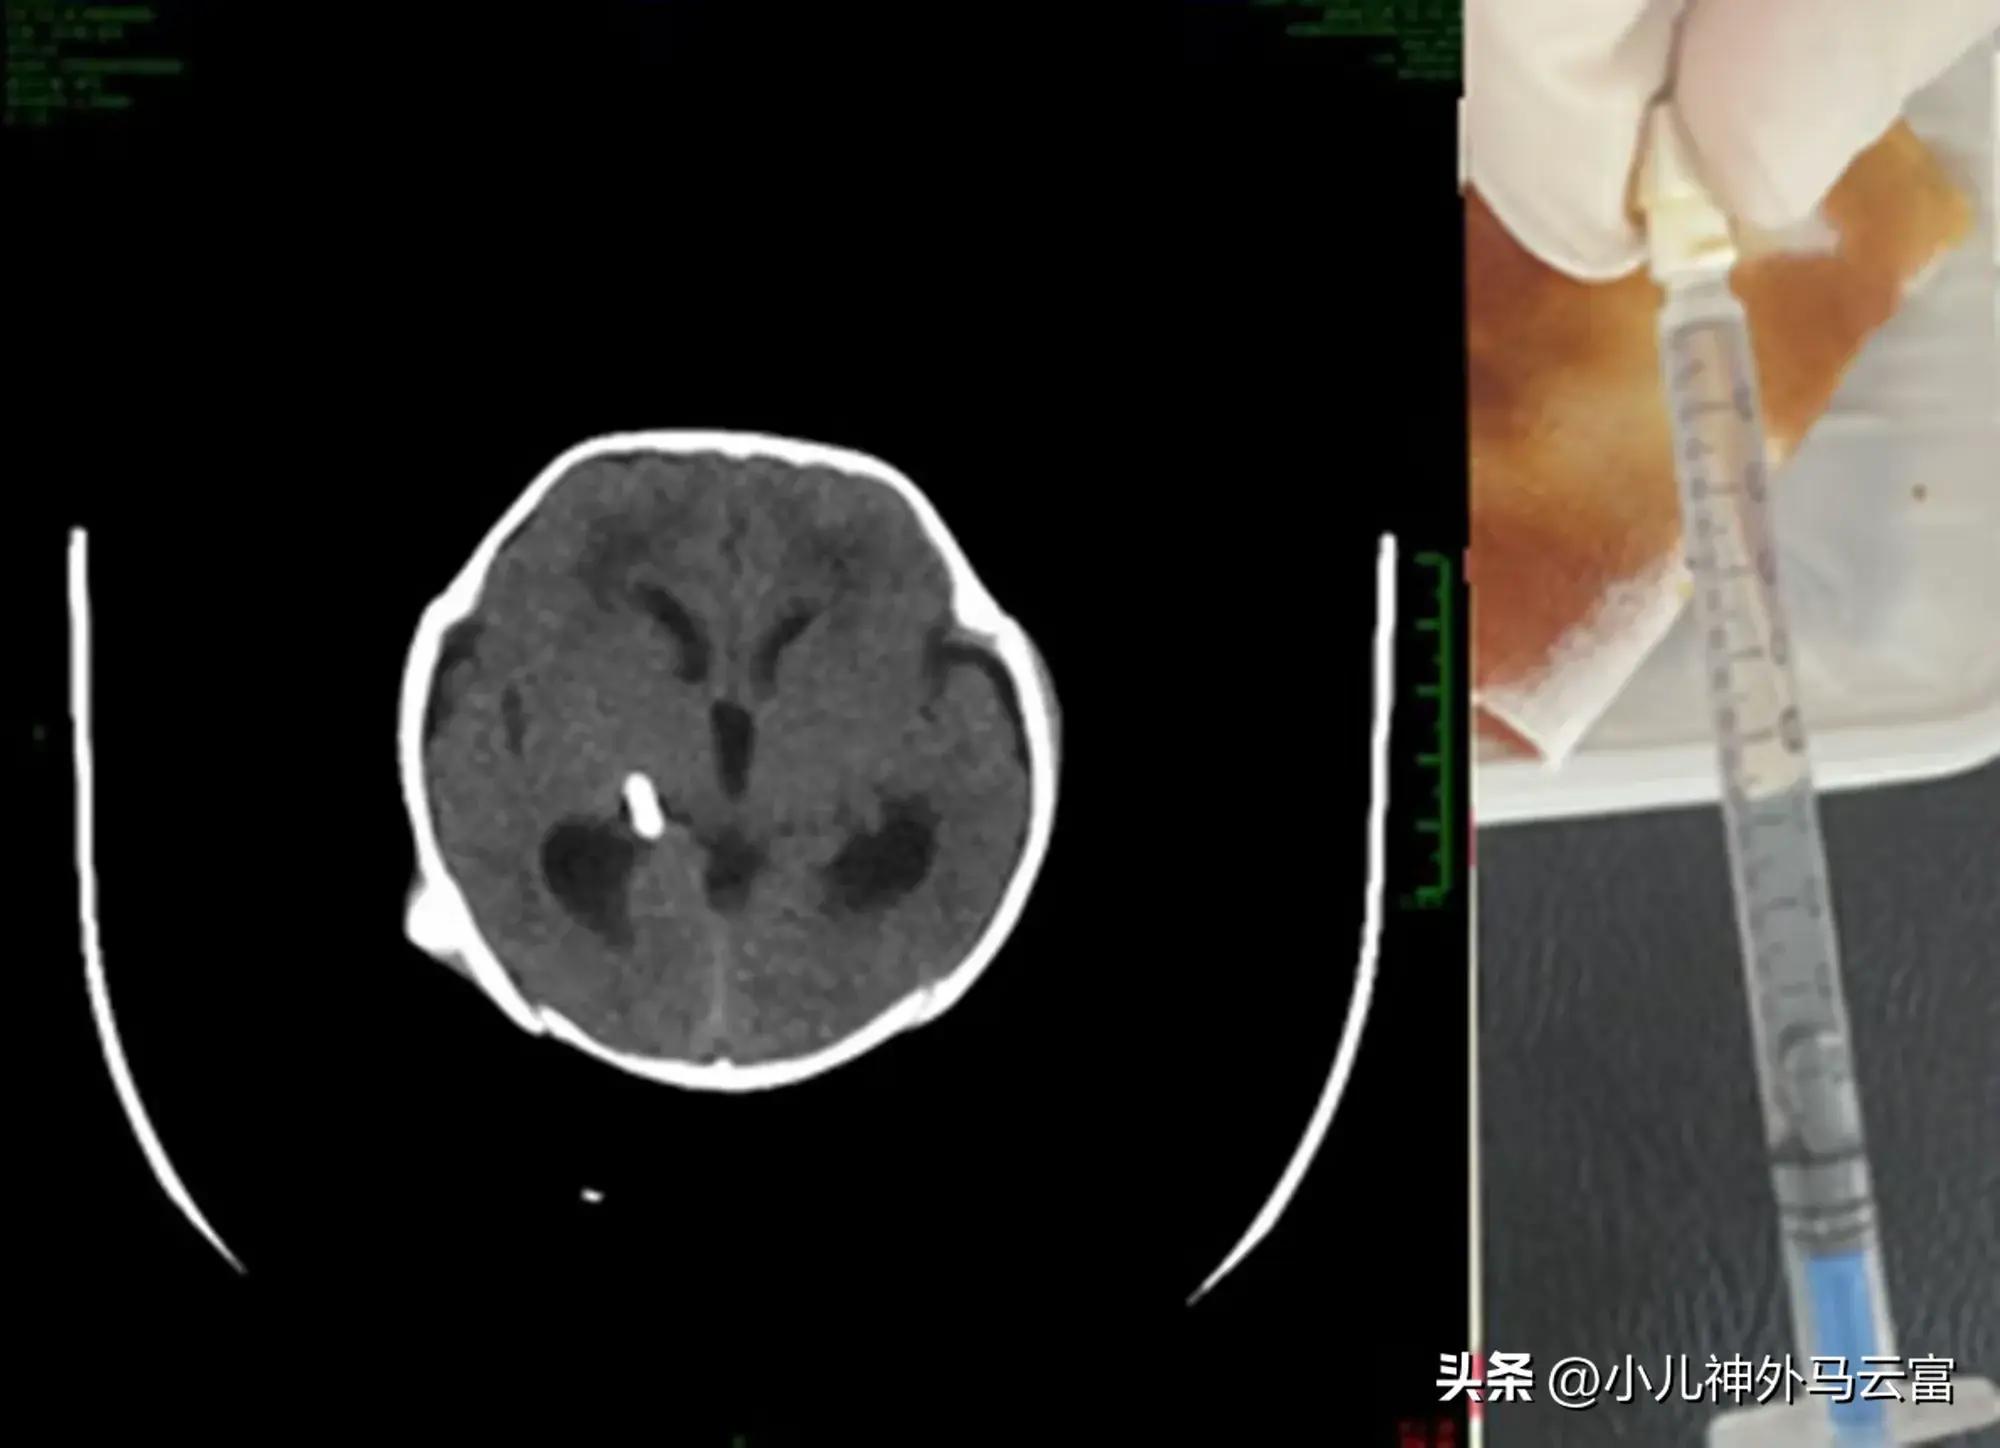

腦室腹腔外引流術中腦脊液渾濁黃色

經過小兒神經外科醫生的轉業用藥和腦脊液持續引流,腦室腹腔外引流每天引流量約40-80毫升腦脊液,患兒的腦室縮小明顯,腦脊液蛋白定量從3.17g/L 降至0.58g/L,腦脊液葡萄糖含量從0.12mmol/L 提升至1.45mmol/L,腦脊液顏色由黃色轉爲清亮無色。

腦室外引流術後一個月,腦脊液清亮無色

2024.7.25CT腦室明顯縮小。

經過持續引流和治療,腦脊液顏色由渾濁黃色轉變爲清亮無色。

如上圖。